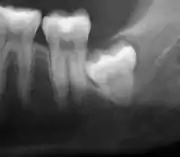

Coronectomy of impacted wisdom tooth post-op xray showing root remnants (red arrow) and inferior alveolar nerve (green arrow)

Coronectomy is a procedure where the crown of the impacted wisdom tooth is removed, but the roots are intentionally left in place. It is indicated when there is no disease of the dental pulp or infection around the crown of the tooth, and there is a high risk of inferior alveolar nerve injury.[31]

Coronectomy, while lessening the immediate risk to the inferior alveolar nerve function has its own complication rates and can result in repeated surgeries. Between 2.3% and 38.3% of roots loosen during the procedure and need to be removed and up to 4.9% of cases require reoperation due to persistent pain, root exposure or persistent infection. The roots have also been reported to migrate in 13.2% to 85.9% of cases.[31]